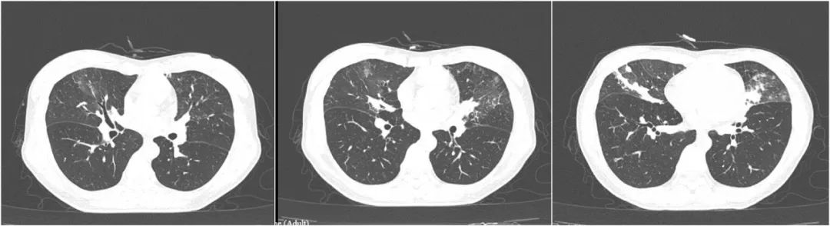

4月前CT: